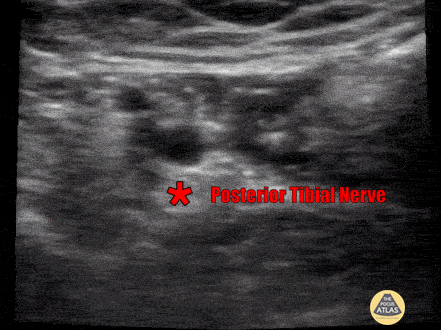

Posterior Tibial Nerve Block Foot and heel pain after missing a jump while skiing. XR showed calcaneal fracture. Pain not relieved by IV analgesics, posterior tibial nerve performed proximal to medial malleolus with complete resolution of pain. Nerve seen inferior to artery. Watch as fluid surrounds nerve. Use in-plane approach to avoid vasculature and avoid intraneural injection. Submitted by Dr. Miguel Agrait Gonzalez, University of Puerto Rico